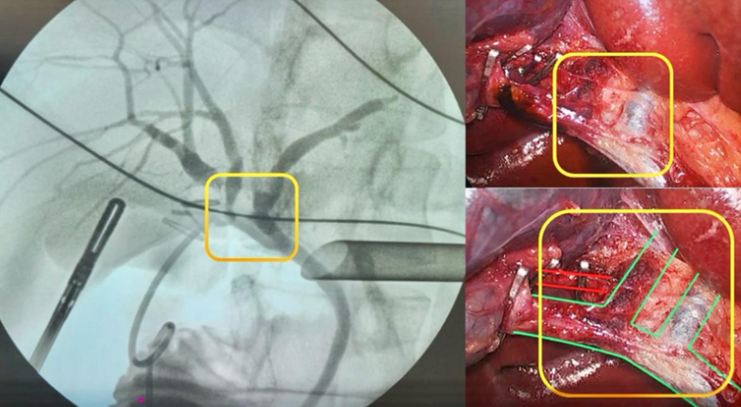

Resumo audio (Português (Brasil)) - Hepatectomía derecha en dos tiempos con ligadura portal y partición hepática asistida por radiofrecuencia (RALPPS) mediante abordaje laparoscópico

Gonzalo San Martín, Patricio Vanerio, Sofía Mansilla, Alejandro Ettlin, Martín Abelleira, Florencia Rodríguez, Martín Harguindeguy

ecir.urug.10.1.3